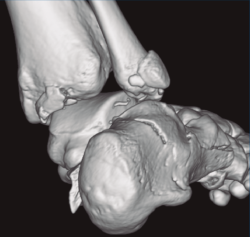

Figura 3. Desplazamiento entre fragmento anteromedial (sustentaculum tali) y posterolateral (tuberosidad).

Se trata de un varón de 19 años que ingresa en reanimación tras precipitarse desde una altura de aproximadamente 10 metros. El paciente presenta una fractura estallido de L3 con afectación del canal medular junto con una fractura del vértice inferior de L4, así como una fractura luxación de calcáneo, asociada a una fractura del maléolo peroneo y del maléolo tibial posterior (Figuras 1 a 6) diagnosticadas mediante TC total body (por eso no se dispone de radiografías simples al momento del ingreso). Como podemos comprobar, se trata de una fractura de doble trazo de tipo hundimiento/depresión de la carilla articular (Figuras 5 y 6).

Figura 4. Luxación fragmento posterolateral.

Figura 5. Fractura maléolo peroneo, luxación astrágalo, fractura de doble trazo en calcáneo.

Figura 6. Fractura de doble trazo; se evidencia afectación de la articulación calcaneocuboidea.